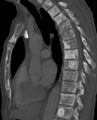

If already having grown large, a prostate cancer may first be detected on CT scan.